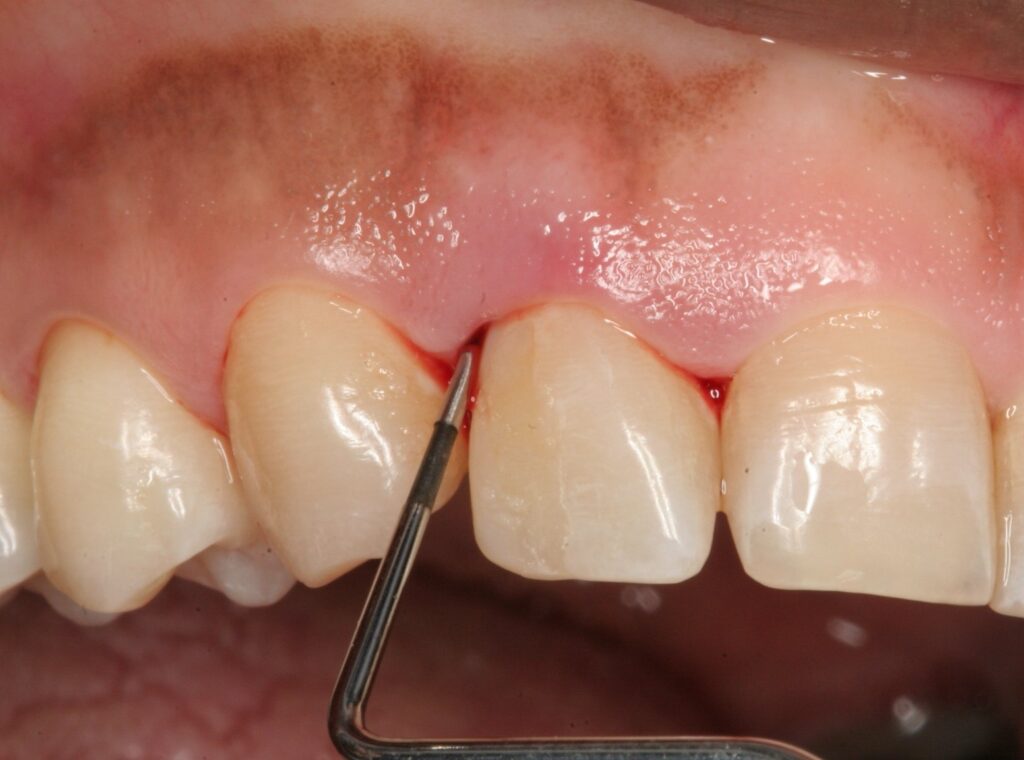

Кровоточивість ясен - часта проблема, яка часто є "дзвіночком" про наявність запалення або ранню стадію хвороби ясен. В такому випадку найкращим рішенням є консультація зі спеціалістом - лікарем-стоматологом, однак деякі природні методи все ж здатні допомогти зменшити кровотечу, а також зміцнити ясна в домашніх умовах. Головне - робити все правильно і регулярно. Детальніше про це розповість "Ми-Україна".

Наостанок додамо, що значно покращити стан ясен можна й натуральними домашніми методами. Особливо, якщо проблема перебуває на початковій стадії. Однак пам'ятайте, якщо кровоточивість не зникає впродовж кількох тижнів - не зволікайте і обов’язково зверніться до стоматолога.